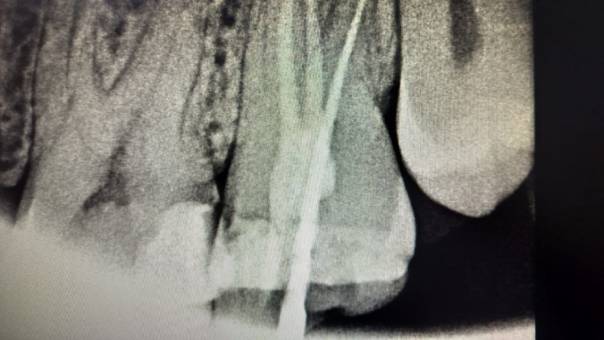

Clinical and Radiographic Findings:

On examination, mild tenderness was noted when

tapping on tooth 27. A radiographic evaluation

revealed that the distal canal of the tooth had been

inadequately treated and left unfilled. This had led

to a localized periapical infection.

Unfilled distal canal pre-operation